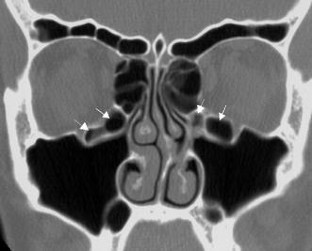

Fig. 3